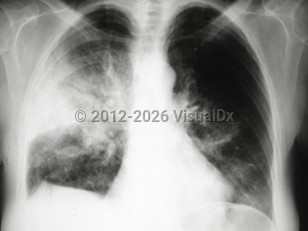

LegionellosisLegionellosis